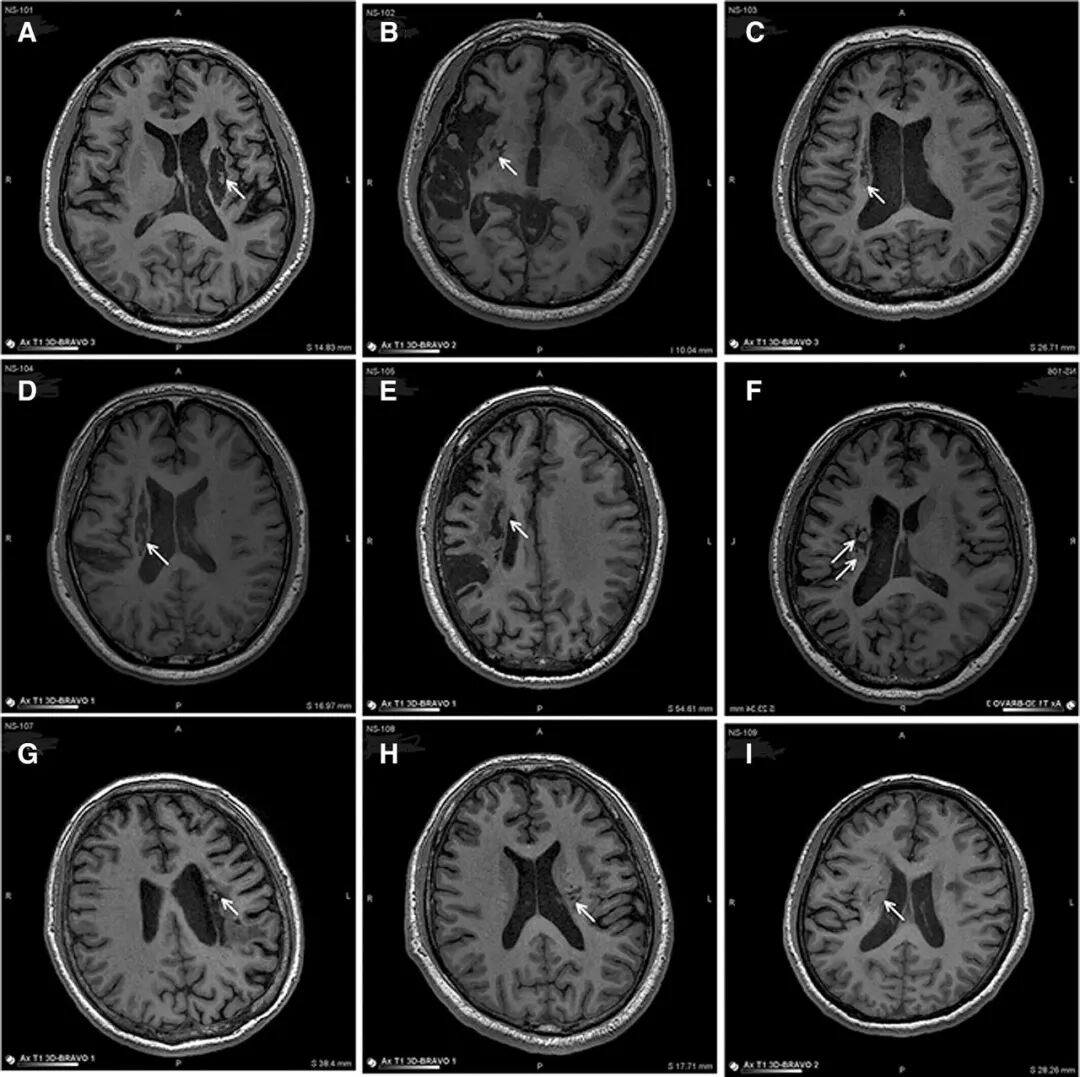

△ 9例患者的影像学显示病变区域的组织都发生了明显变化

影像学研究的结果表明,干细胞输入区出现了新的神经组织,这也证明了干细胞治疗偏瘫性脑卒中拥有一定的临床益处。目前,关于干细胞治疗脑中风的临床研究正在全球范围内开展,也有许多已经开展了更为深入的临床应用,随着我国近年来细胞政策的逐渐开放,政府的支持与鼓励,以及细胞政策的不断完善,都将推动这一进程快速向前,让干细胞能够惠及更多脑中风患者,为他们解除病痛烦恼。